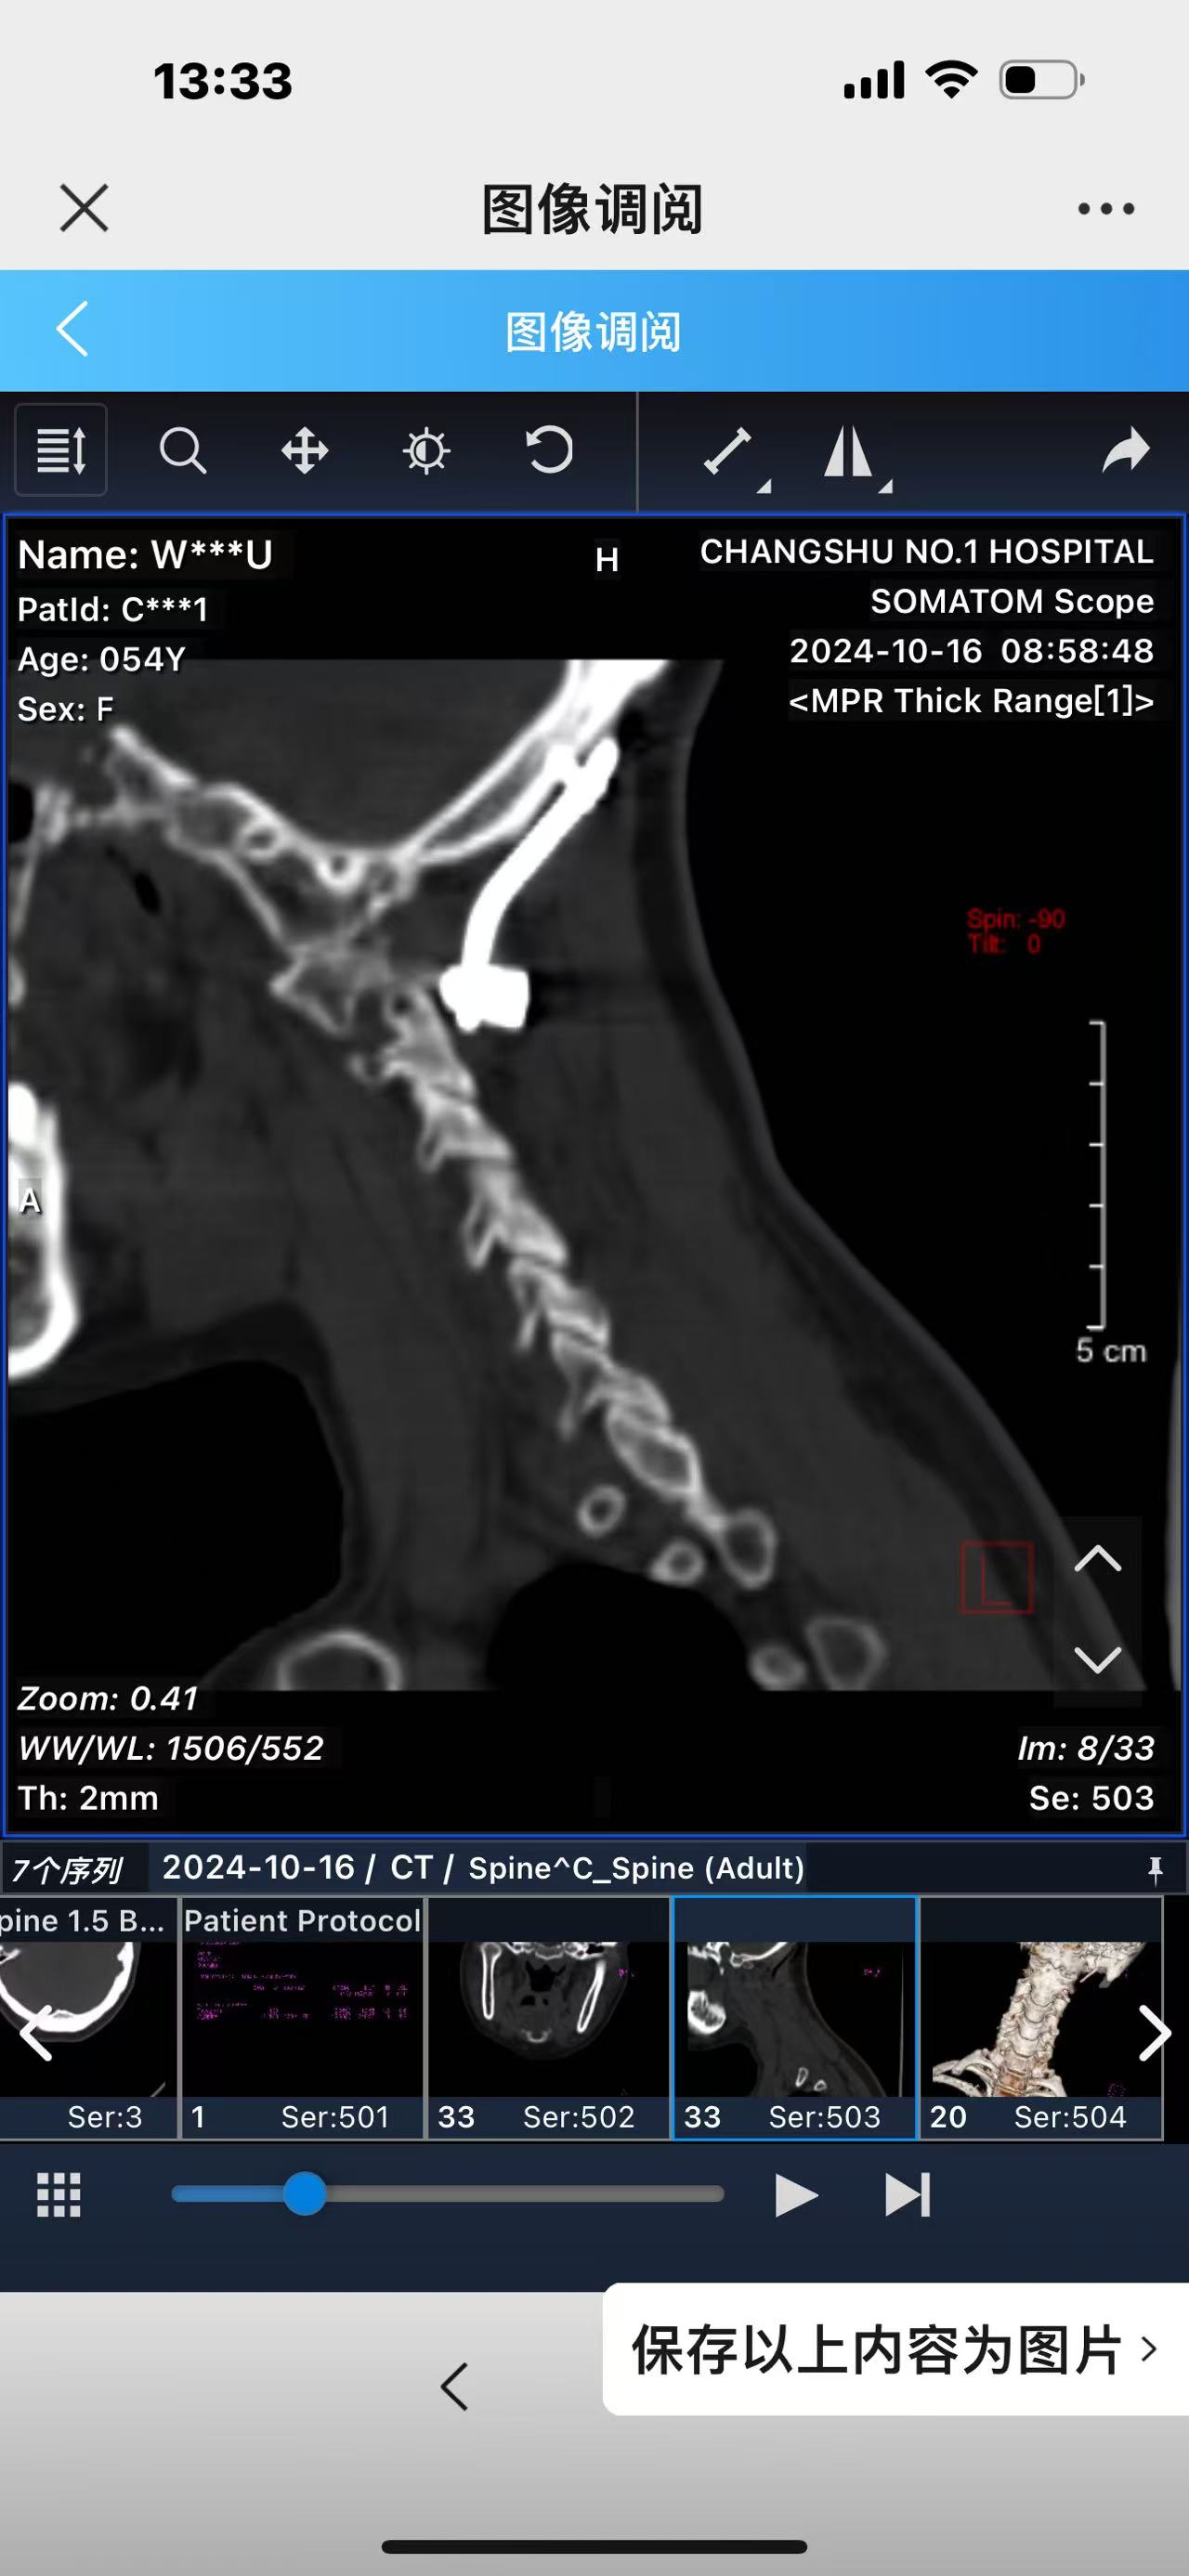

• 诊断:寰枢椎脱位,颅底凹陷

• 术后影像:

• 2024.10.20,复查,对位良好,偶尔会肩甲骨酸,坐下就不酸。